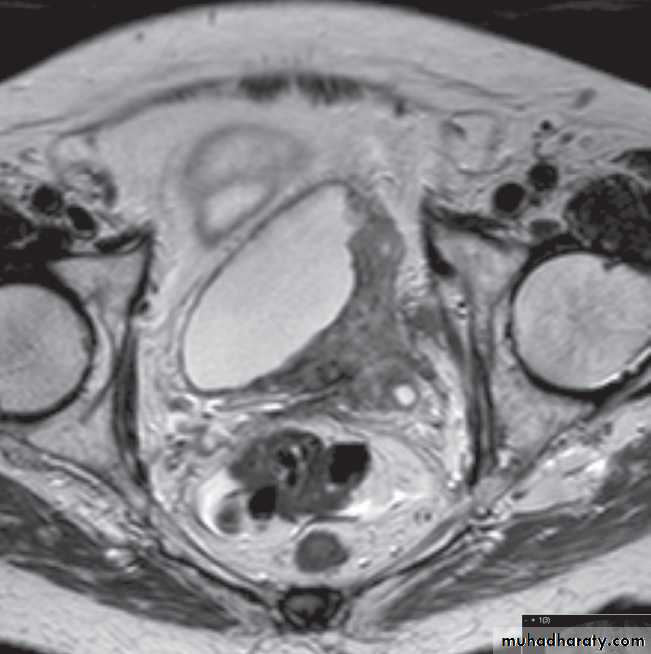

On CT and MRI, a bladder tumour is seen as a soft tissue mass projecting from the wall or a focal thickening of the bladder wall . As the diagnosis is best established by cystoscopy and biopsy, the roles of CT and MRI are to stage the tumour. CT and MRI can determine the spread of tumour beyond the bladder wall and assess lymph node involvement .